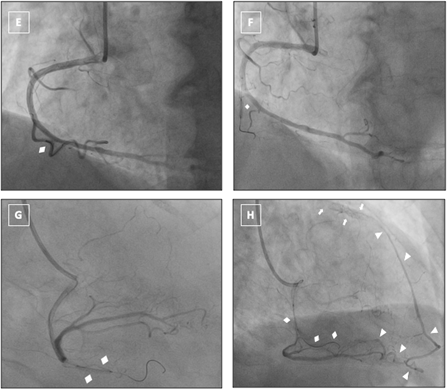

To functionally assess the completeness of collateral perfusion and uncover potential secondary channels, a selective balloon occlusion test was performed. A 2.0 × 15-mm semi-compliant balloon was advanced into the AM branch over a 0.014-inch guidewire (Figure E) and inflated to occlusive pressure to transiently obstruct the dominant epicardial collateral supplying the LAD (Figure F and G). Repeat RCA injections during balloon inflation failed to reveal any supplementary collateral filling of the LAD, thereby confirming the RCA-AM as the sole conduit of retrograde flow (Videos 5 and 6). Following balloon deflation, collateral flow promptly resumed, and the patient remained hemodynamically stable (Figure H, Video 7).